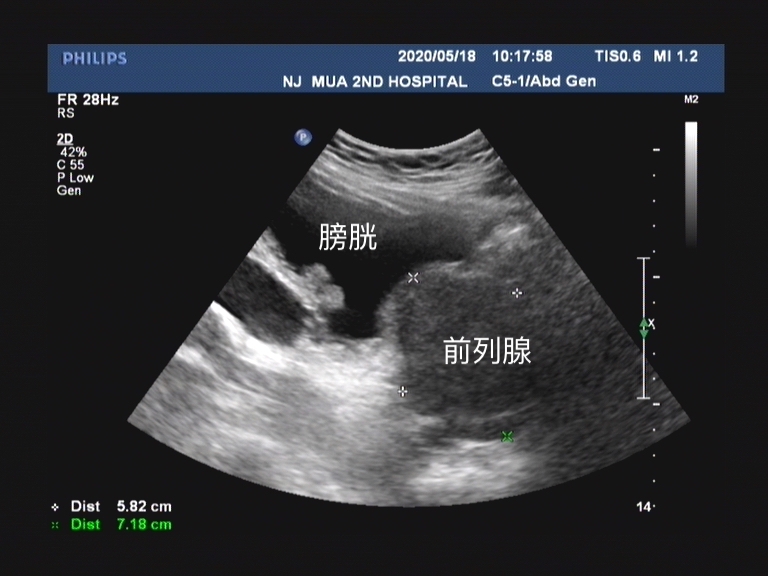

其实和临床我们确诊前列腺增生这个病有一些区别的地方在于 ,彩超给予患者前列腺增生这个诊断时候,是通过测量患者的前列腺体积。 超声检查可以了解 前列腺的形态、体积、有无异常回声、凸入膀胱的程度和残余尿量 。 前列腺体积的测量公式为0.52*前后径*左右径*上下径。

超声的诊断标准中, 如果测量的前列腺体积超过4cm*3cm*2cm时 ,在报告中就会描述为前列腺增生。因为患者的前列腺体积的确增大了。 而前列腺增生最主要的病理生理改变就是由于体积增大导致后尿道延长、受压变形、狭窄和尿道阻力增加。 这种前列腺体积增大就意味着从超声的角度可以诊断患者为前列腺增生。

同时彩超检查所折射出的前列腺体积增大, 并不是患者需要接受药物治疗或手术治疗的绝对指标。 现阶段临床评估前列腺增生临床进展的危险因素(感兴趣的可以看下之前文章)包括 年龄、血清PSA、前列腺体积、最大尿流率、残余尿量、症状评分、前列腺慢性炎、代谢综合征及膀胱内前列腺突入度。 前列腺体积只是威胁前列腺增生患者临床症状进展的一个临床指标。